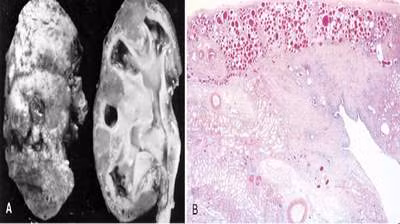

Viêm cầu thận dẫn đến STM ở trẻ em chiếm tỉ lệ cao nhất, trong đó đáng lưu ý là nguyên nhân viêm cầu thận liên quan đến nhiễm khuẩn (viêm cầu thận cấp). Bệnh thường gặp ở trẻ em sau viêm họng hoặc viêm da. Các nghiên cứu ở nước ta cho thấy có 5 - 10% bệnh nhi, bệnh tiếp tục tiến triển mạn tính và gây suy thận sau 10 năm bị viêm cầu thận cấp. Có 80% trẻ bị viêm cầu thận cấp xảy ra sau viêm họng hoặc viêm da do liên cầu khuẩn, số còn lại do các vi khuẩn khác. Độ tuổi thường gặp là 6-9, bệnh xảy ra quanh năm nhưng tập trung nhiều vào các tháng 9 - 12. Nghiên cứu sinh thiết thận ở trẻ viêm cầu thận cấp sau 10 - 15 năm cho thấy có tới 70% trường hợp có tổn thương xơ cứng cầu thận từng phần hoặc hoàn toàn, trong đó 30 - 40% có biểu hiện triệu chứng lâm sàng. Riêng ở tỉnh Vĩnh Phúc trong 10 năm (1995 - 2005) có 274 bệnh nhi bị viêm cầu thận cấp vào điều trị tại bệnh viện tỉnh, trong đó có 5,4% bệnh nhi bệnh tiến triển thành mạn tính và suy thận, sau 7 - 10 năm có 1,8% bệnh nhi phải lọc máu chu kỳ (Tạ Ngọc Cầu, Hà Hoàng Kiệm). Nếu làm tốt công tác chăm sóc sức khỏe, vệ sinh thân thể, vệ sinh răng miệng, đề phòng và điều trị sớm nhiễm khuẩn họng và da thì có thể làm giảm được bệnh này, góp phần làm giảm tỉ lệ STM ở trẻ em.

- Bệnh thận bẩm sinh gặp 16,2% số trẻ STM, trong đó bệnh thận nang chiếm 1,9% có thể phát hiện sớm bằng siêu âm thận. Hội chứng Alport chiếm 1,5% - đây là hội chứng bệnh lý có tính chất gia đình, bệnh biểu hiện bằng suy thận và 50% bệnh nhi có kèm theo điếc. Ngoài ra có thể gặp các bệnh thận bẩm sinh khác như Cystinosis, Oxalosis.